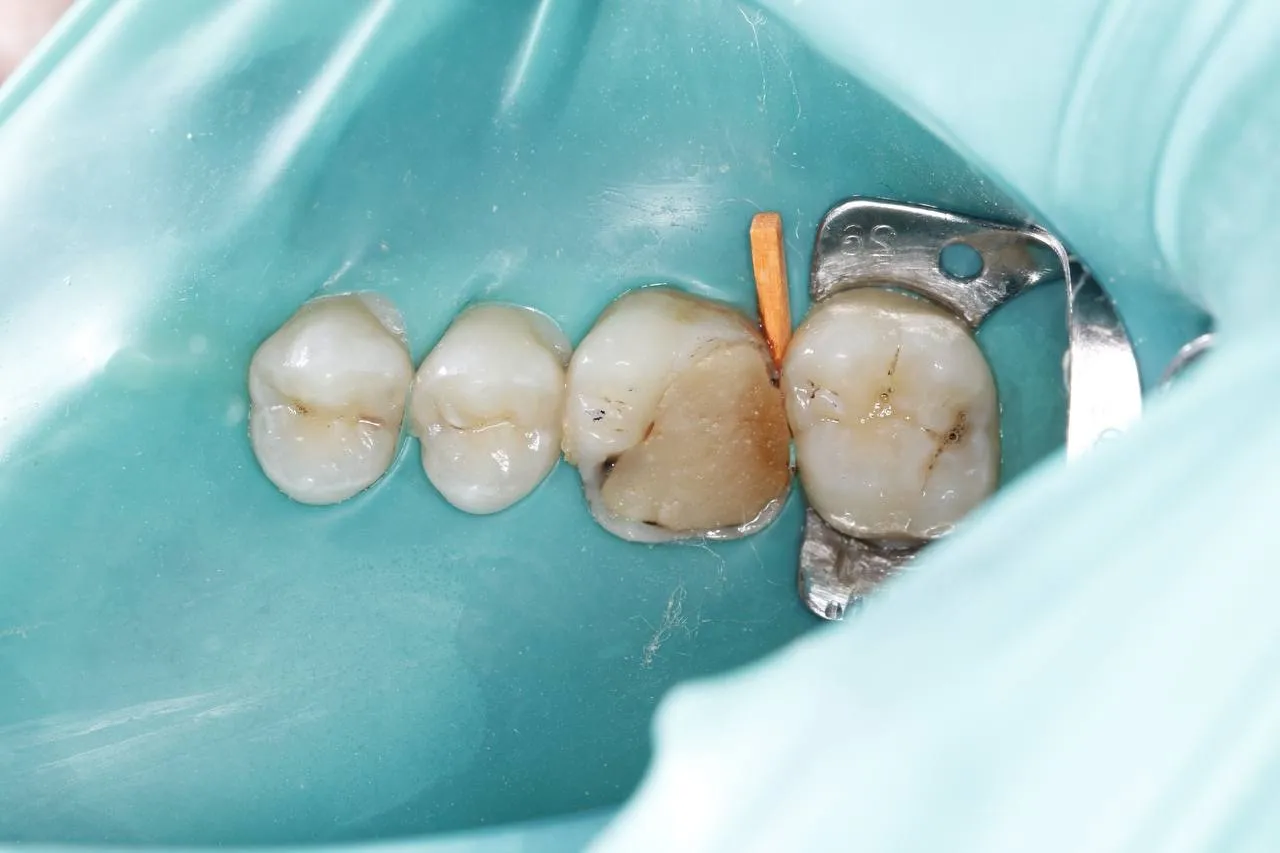

Лікування карієсу під мікроскопом зуба 16